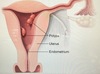

What is Asherman syndrome?

[Intrauterine adhesions and endometritis] from uterine instrumentation (D&C) ➜ [cyclic abd pain and secondary amenorrhea] immediately following instrumentation